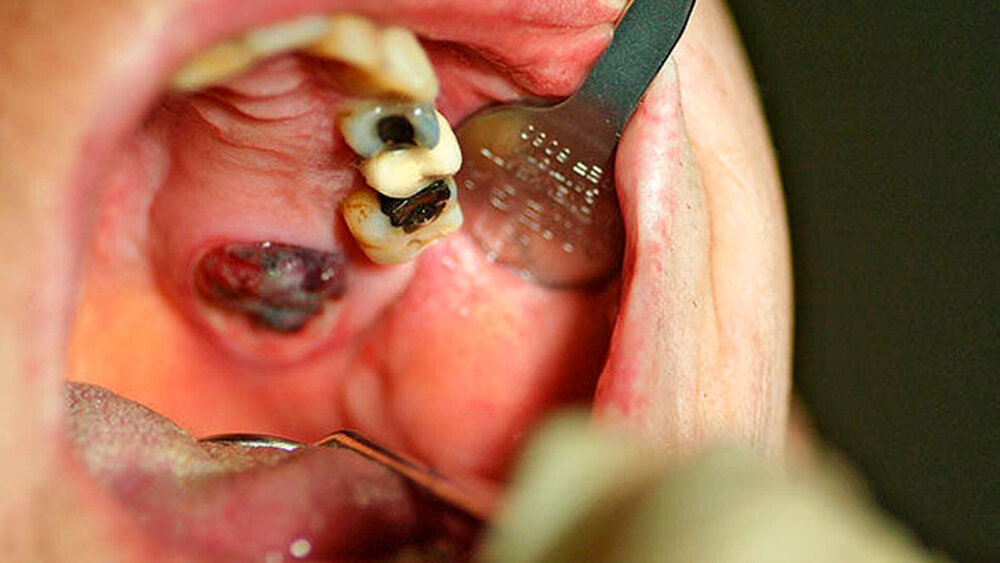

Zum Zeitpunkt der Untersuchung zeigte sich im linken Oberkiefer palatinal regio 26/27 ein livider braun-rötlicher Tumor von etwa zwei Zentimeter Größe mit Verdrängung der fixierten Gingiva nach krestal. Nach palatinal-medial war das Bindegewebe unter reizloser Schleimhaut aufgetrieben (Abbildung 1). In der Bildgebung mittels Panoramaschichtaufnahme zeigte sich in der interessierenden Region eine Verschattung der linken basalen Kieferhöhle mit Auflösung des krestalen Knochens im Molarenbereich. Des Weiteren war ein retinierter Zahn 48 und ein horizontal-vertikaler Knochenabbau bei bekannter Parodontitis zu erkennen (Abbildung 2). Zur weiteren Diagnostik wurde eine Computertomografie des Kopfes und bei Verdacht auf mögliche Metastasierung der vorbekannten Malignome eine Computertomografie des Thorax und Abdomens durchgeführt. Hierbei zeigte sich die bereits diagnostizierte Raumforderung im Bereich der linken basalen Kieferhöhle mit partieller Auflösung des molarennahen Knochens und einer weichteildichten Raumforderung im Bereich der basalen Kieferhöhle. Die kranialen Anteile der Kieferhöhle waren belüftet (Abbildung 3). Ein Anhalt für eine Metastasierung oder ein Rezidiv des Urothel- bzw. Prostatakarzinoms bestand nicht. In dem durch eine Inzisionsbiopsie in Lokalanästhesie entnommenem Gewebe zeigte sich histologisch eine teils glandulär, teils kribriform konfigurierte epitheliale Proliferation mit teils basophilem Stroma. Es lag eine deutliche Positivität für CK7 und S100 ohne Färbereaktion für CK5/6 vor. Somit entsprach der Befund dem eines kanalikulären Adenoms. Der Tumor wurde in Intubationsnarkose entfernt. Zur Kieferhöhle bestand eine dünne knöcherne Abgrenzung, die belassen wurde. Eine endoskopische Untersuchung über den mittleren Nasengang zeigte bis auf zwei kleinen Schleimretentionszysten oberhalb der Läsion – die jeweils entfernt wurden – keine weiteren Auffälligkeiten. Der Defekt wurde durch eine Einlagerung des Bichat’schen Fettkörpers und eines Mukoperiost-Lappens von vestibulär gedeckt. Die finale histologische Beurteilung bestätigte die Diagnose und eine vollständige Entfernung. Nach einem unkomplizierten postoperativen Heilungsverlauf zeigte der Patient in der klinischen Nachsorge nunmehr sechs Monate nach Operation keinen Anhalt für ein Rezidiv.

Das kanalikuläre Adenom ist ein seltener benigner Tumor, der etwa ein bis drei Prozent aller Speicheldrüsentumore ausmacht [Peraza et al., 2017] Es präsentiert sich typischerweise, wie auch im vorgestellten Fall, als eine submuköse Raumforderung mit lividem Aussehen im Falle eines Schleimhautdurchbruchs. Eine intakte Schleimhautbedeckung ist ebenso möglich. Anamnestisch berichten die Patienten in der Regel über eine langsame, oft mehrmonatige Größenzunahme. Das im vorgestellten Fall kurzzeitige Wachstumsintervall ist nicht charakteristisch für diese Erkrankung. Symptome wie Missempfindungen und Schmerzen treten selten auf.